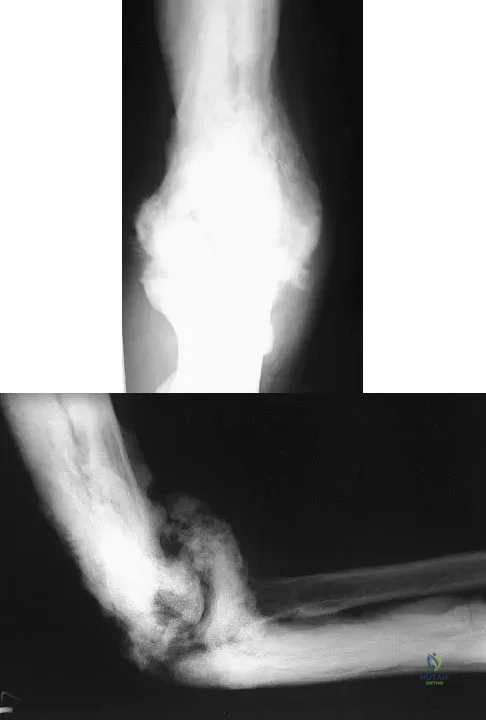

A 28-year-old man sustained numerous injuries in an accident including a dislocation of the elbow and a severe closed head injury that resulted in unconsciousness. The elbow was reduced in the emergency department. After 1 month of rehabilitation, the patient reports pain and stiffness. A radiograph is shown in Figure 23. Management should now consist of

Correct Answer: open reduction, heterotopic bone excision, anterior and posterior capsular releases, and a hinged elbow fixator.

In a young individual with a chronic dislocation of the elbow and heterotopic bone formation, the treatment of choice is open reduction, heterotopic bone excision, anterior and posterior capsular releases, and a dynamic hinged fixator to begin protected early postoperative range of motion. It is important to understand that the fixator protects the reconstruction and allows early range of motion, but it does not maintain the reduction and should not be expected to do so. Pin fixation across the elbow delays early motion and is not recommended. Total elbow arthroplasty is not indicated, and ulnohumeral arthroplasty is for a primary arthritic condition. Garland DE, Hanscom DA, Keenan MA, et al: Resection of heterotopic ossification in the adult with head trauma. J Bone Joint Surg Am 1985;67:1261-1269.